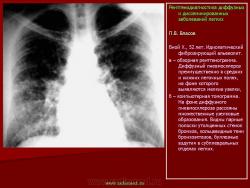

П.В. Власов

При идиопатическом фиброзирующем альвеолите на рентгенограммах обычно выявляется двустороннее симметричное усиление легочного рисунка. В противоположность саркоидозу, для которого характерно преобладание изменений в прикорневых отделах легких, при фиброзирующем альвеолите легочная ткань поражается более равномерно. Отмечено некоторое преобладание из менений в базальных и периферических, субплевральных отделах. Диффузная пролиферация фиброзной ткани ведет к деформации и перестройке архитектоники легочного рисунка по сетчатому типу. В периферических, субплевральных отделах легочный рисунок приобретает вид “пчелиных сот”, формируется картина так называемого “сотового легкого”: утолщенные межальвеолярные, периацинарные и междольковые перегородки охватывают эмфизематозно вздутые дольки и ацинусы. Для фиброзирующего альвеолита типичным является развитие буллезной эмфиземы, которая обычно развивается раньше других изменений легочного рисунка. Эмфизематозные буллы лопаются, вследствие чего иногда возникает спонтанный пневмоторакс, который может повторяться несколько раз. Одним из ранних рентгенологических проявлений идиопатического фиброзирующего альвеолита является диффузное понижение пневматизации типа матового стекла. C.Bergin с соавт. (1990) отметили, что при ИФА нередко наблюдается увеличение бронхопульмональных и медиастинальных лимфатических узлов. Следует однако иметь ввиду, что расширение корней легких при фиброзирующем альвеолите может быть вызвано увеличением калибра магистральных сосудов, вследствие гипертензии в малом круге кровообращения. Описанные признаки легочной гипертензии в далеко зашедшей стадии заболевания сочетаются с картиной так называемого легочного сердца. При фиброзирующем альвеолите вследствие уменьшения объема легких, диафрагма обычно занимает высокое положение. И.В. Васильчук (1985) отметила уменьшение объема легких и высокое положение диафрагмы с ограничением ее подвижности более чем у половины больных с идиопатическим фиброзирующим альвеолитом. Признаки легочной гипертензии отмечены у 30% больных. Нередко появляются дисковидные ателектазы. Функциональные исследования подтверждают наличие высокой степени респираторной недостаточности. Реография позволяет выявить признаки гипертензии малого круга кровообращения и дать ей количественную оценку. Сцинтиграфия может показать значительное понижение капиллярного кровотока, в местах наиболее выраженных изменений рентгенологической картины.